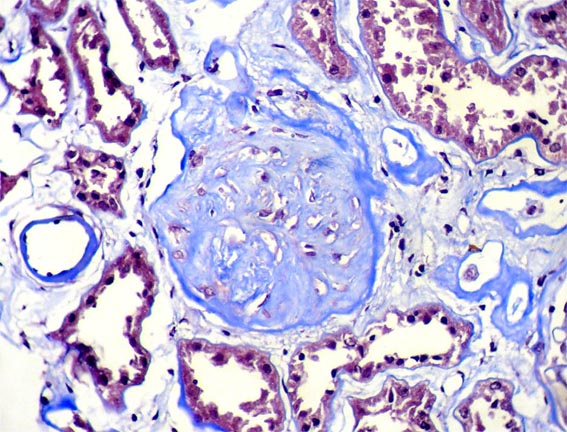

Figura 5.

Glomerulosclerosis global: 5 de 145. Tricrómico de Masson, X400.